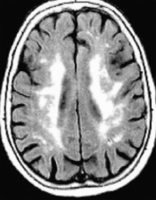

Eine seltene Ursache der hypertrophen Kardiomyopathie – Morbus Fabry // A Rare Cause of Hypertrophic Cardiomyopathy: Fabry’s Disease

Journal für Kardiologie - Austrian Journal of Cardiology 2018; 25 (7-8): 181-184 Volltext (PDF) Summary Abbildungen